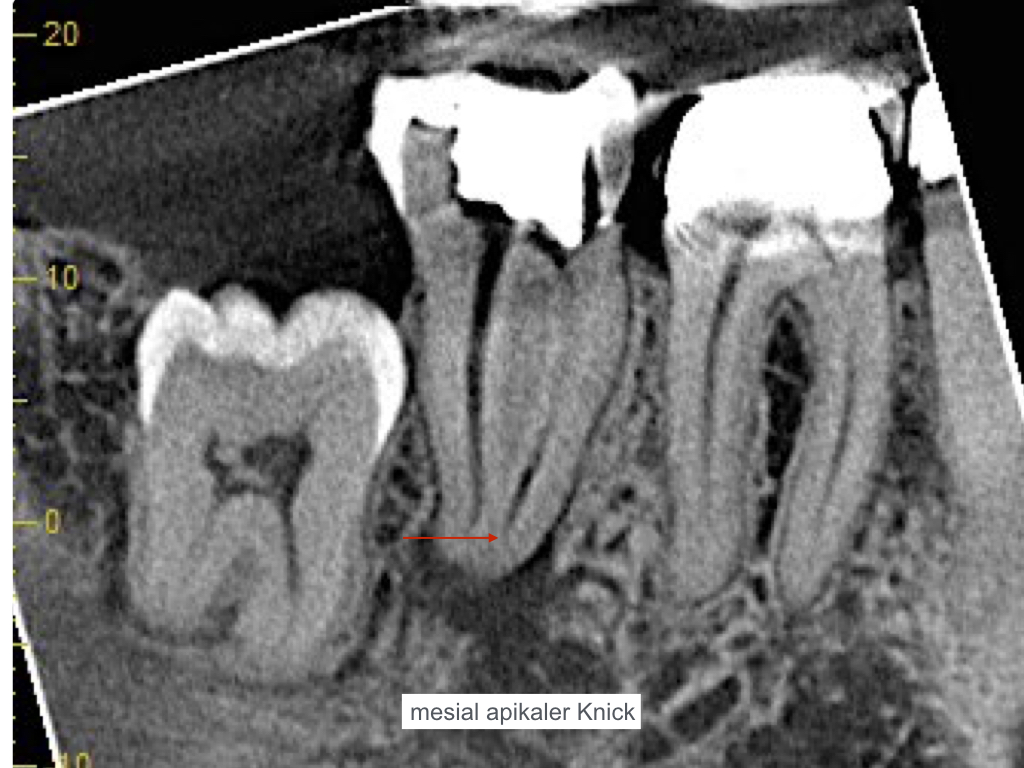

ws-15092016-004

Handinstrumentierung